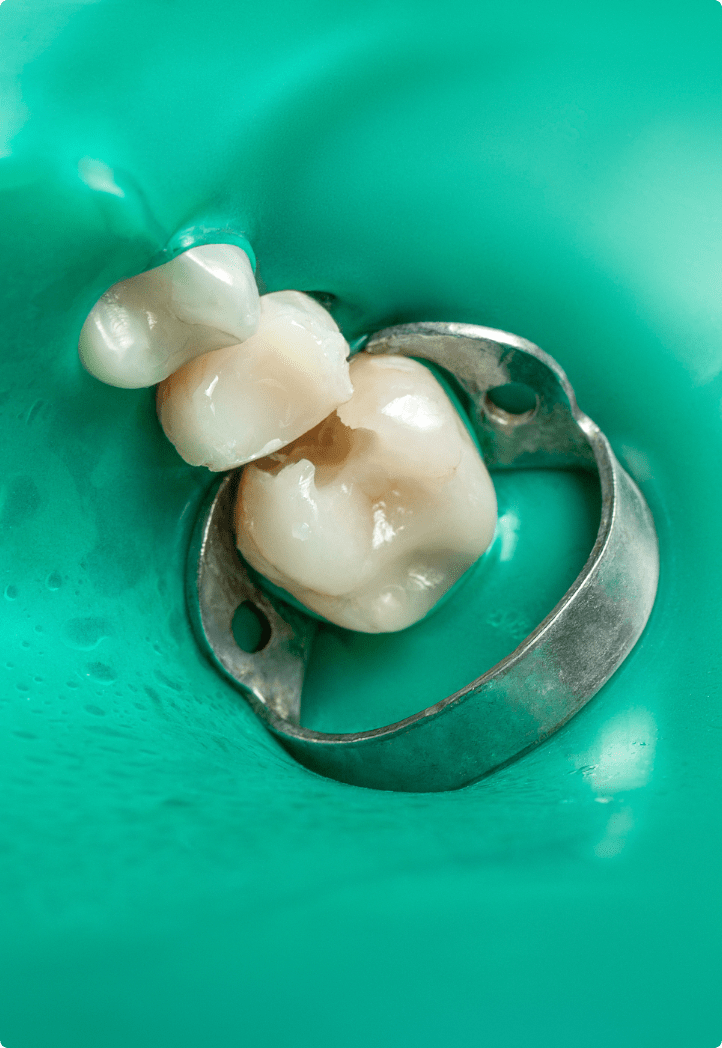

01ラバーダム防湿を用いる

予後を良好にするためには「無菌的治療」が必要と言われています。唾液中には大量の細菌がいるため、治療中に根管の中に唾液が侵入してしまうとせっかく治療して細菌をなくしたところに再び細菌が入ってしまい再感染してしまいます。

それを防ぐためにラバーダム防湿と呼ばれるゴム製のシートを使い、治療する歯を隔離することによって、唾液に含まれる細菌や呼気による湿気を防ぐことができます。現在の根管治療では必須であると言えるでしょう。根管治療後の被せ物治療の際にも、接着力を高めるためにラバーダム防湿が重要になります。

二次虫歯による感染根管治療を行った症例

BEFORE

AFTER

症例概要

年代、性別

50代女性

主訴

右下の歯が噛むと痛い

診断

根尖性歯周炎、歯周炎

治療内容

歯周基本治療、感染根管治療、ファイバーポストを用いた支台築造、フルジルコニアクラウン装着

治療期間

3ヶ月程度

治療リスク

噛み合わせの状態によっては歯根破折を起こすことがある

治療費用

275,000円(税込)